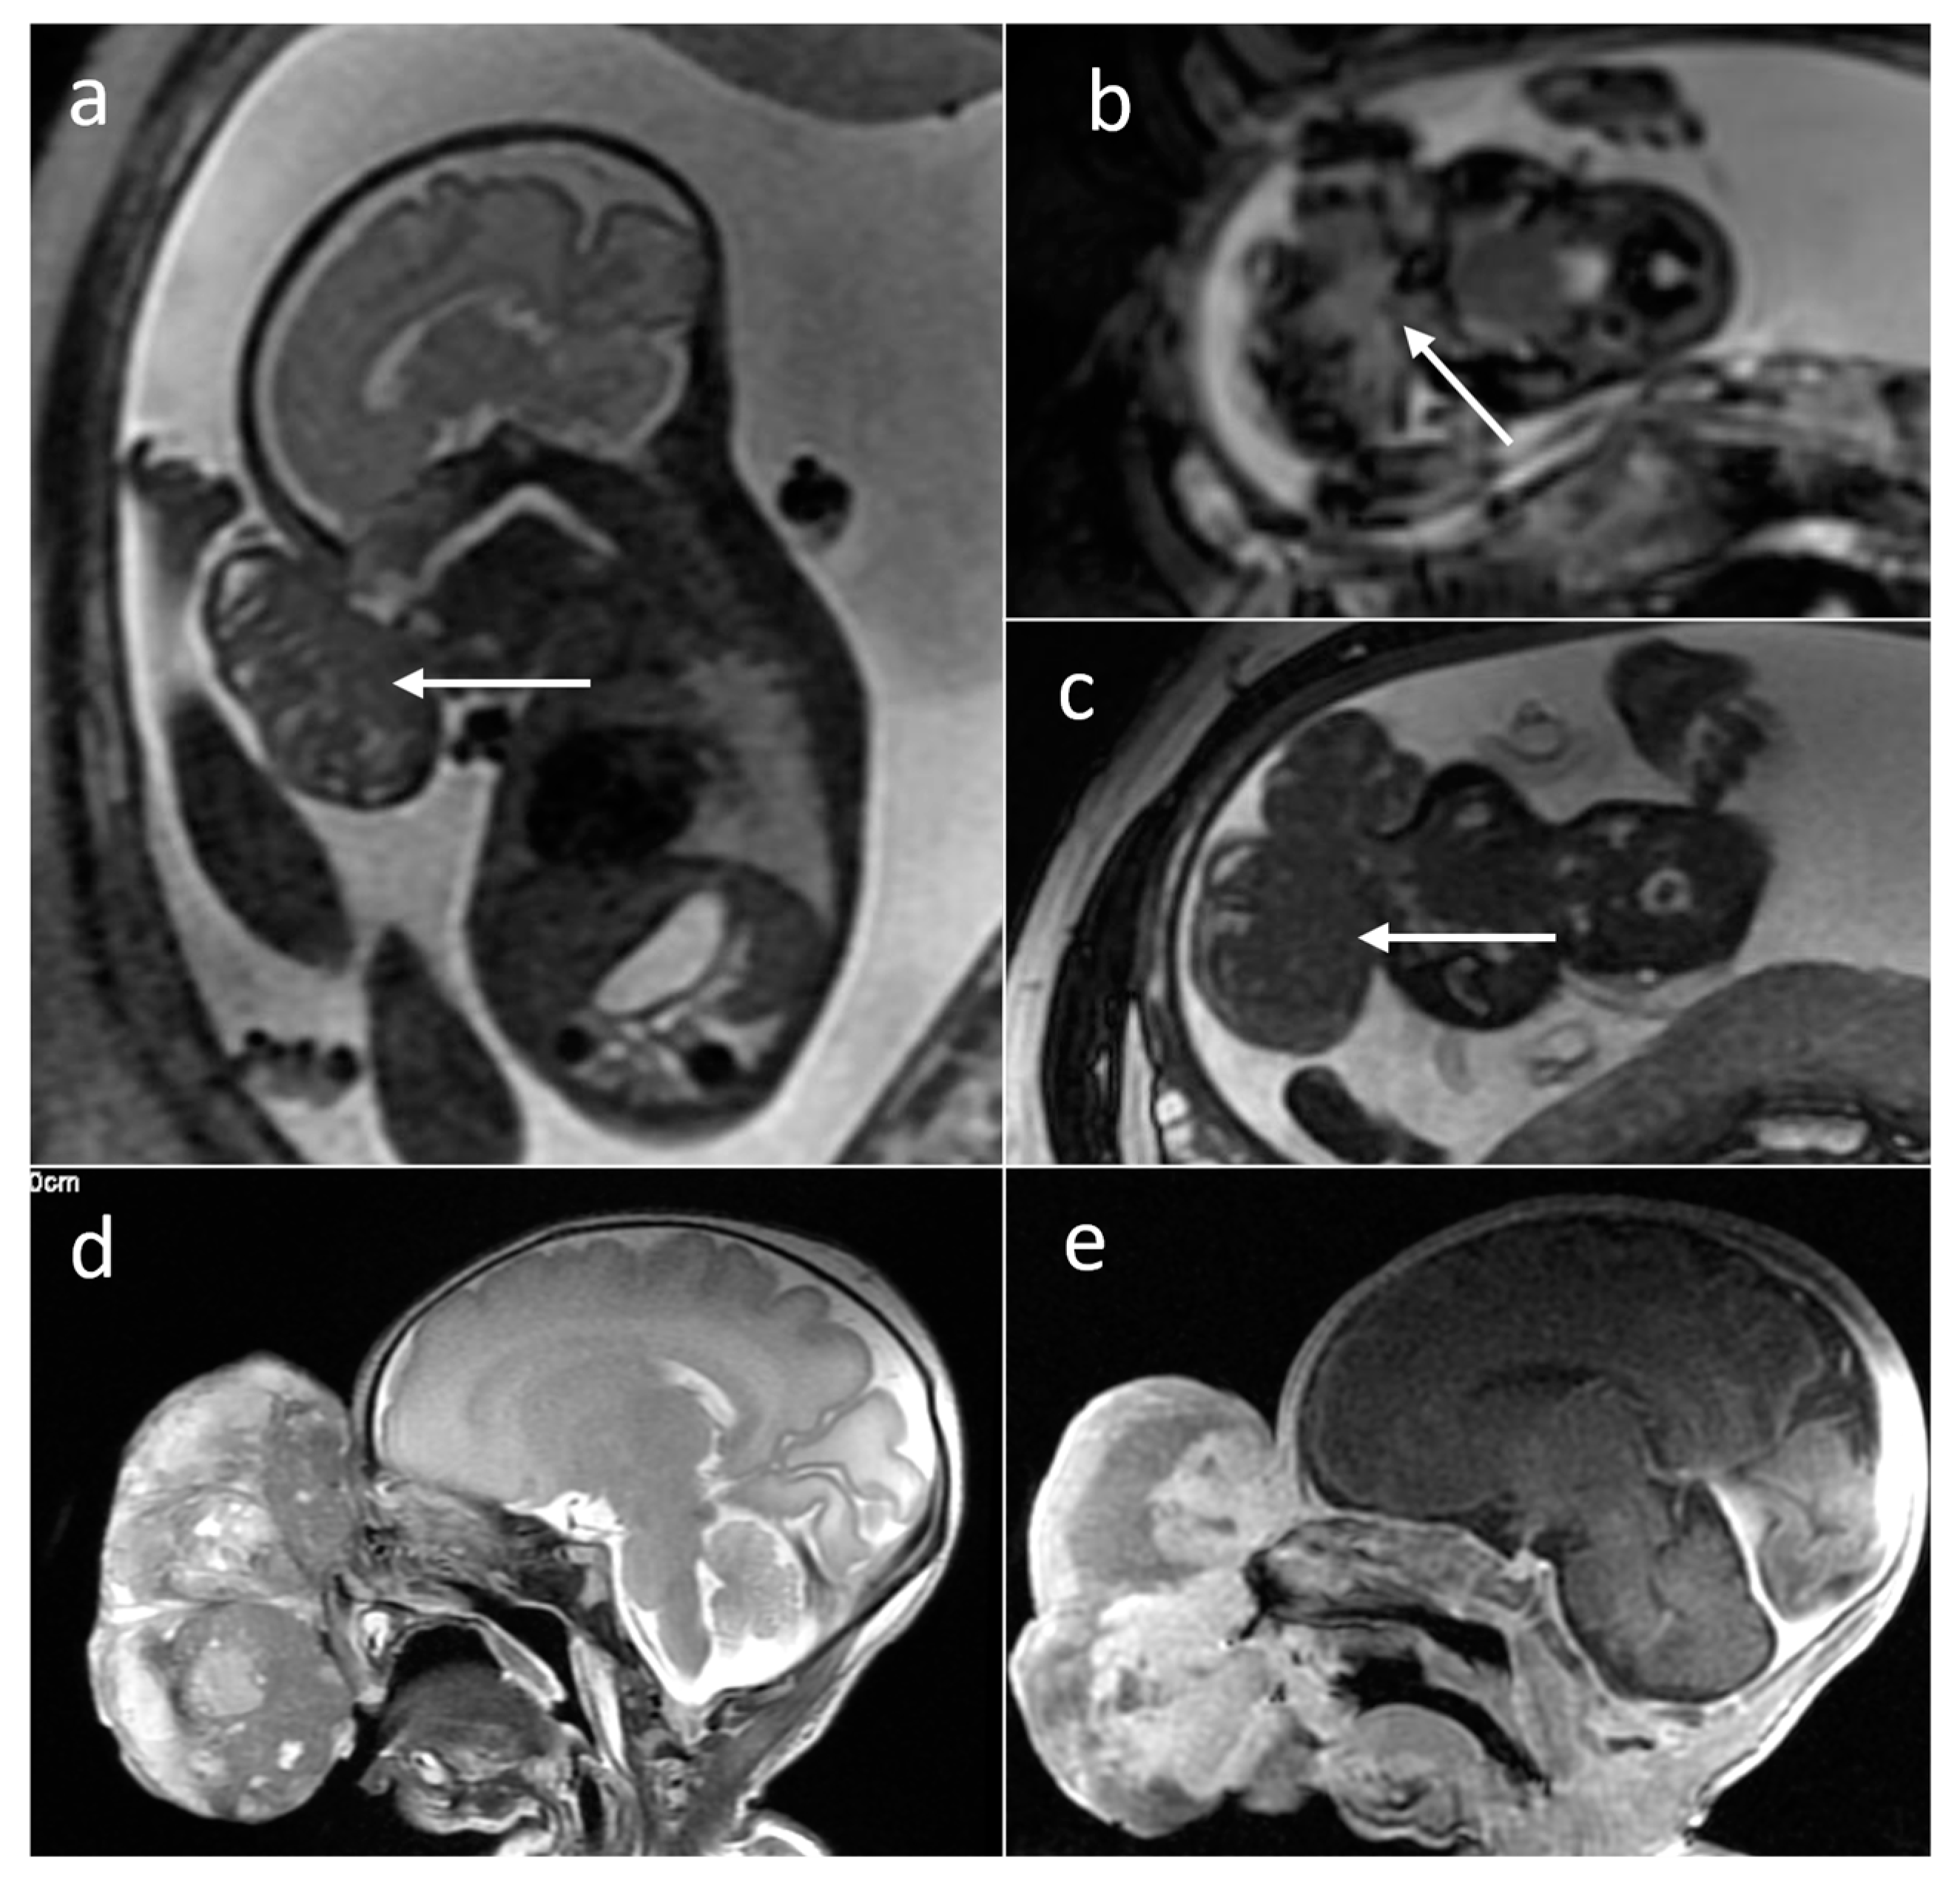

| Rhabdomyoma | heart | 22 | 5.08 [0.1–22] | no | Solid | No | N/A |

| Subependymal giant cell astrocytoma | foramen of Monro | 6 | 0.74 [0.59–0.89] | no | Solid | yes (2/2) | N/A |